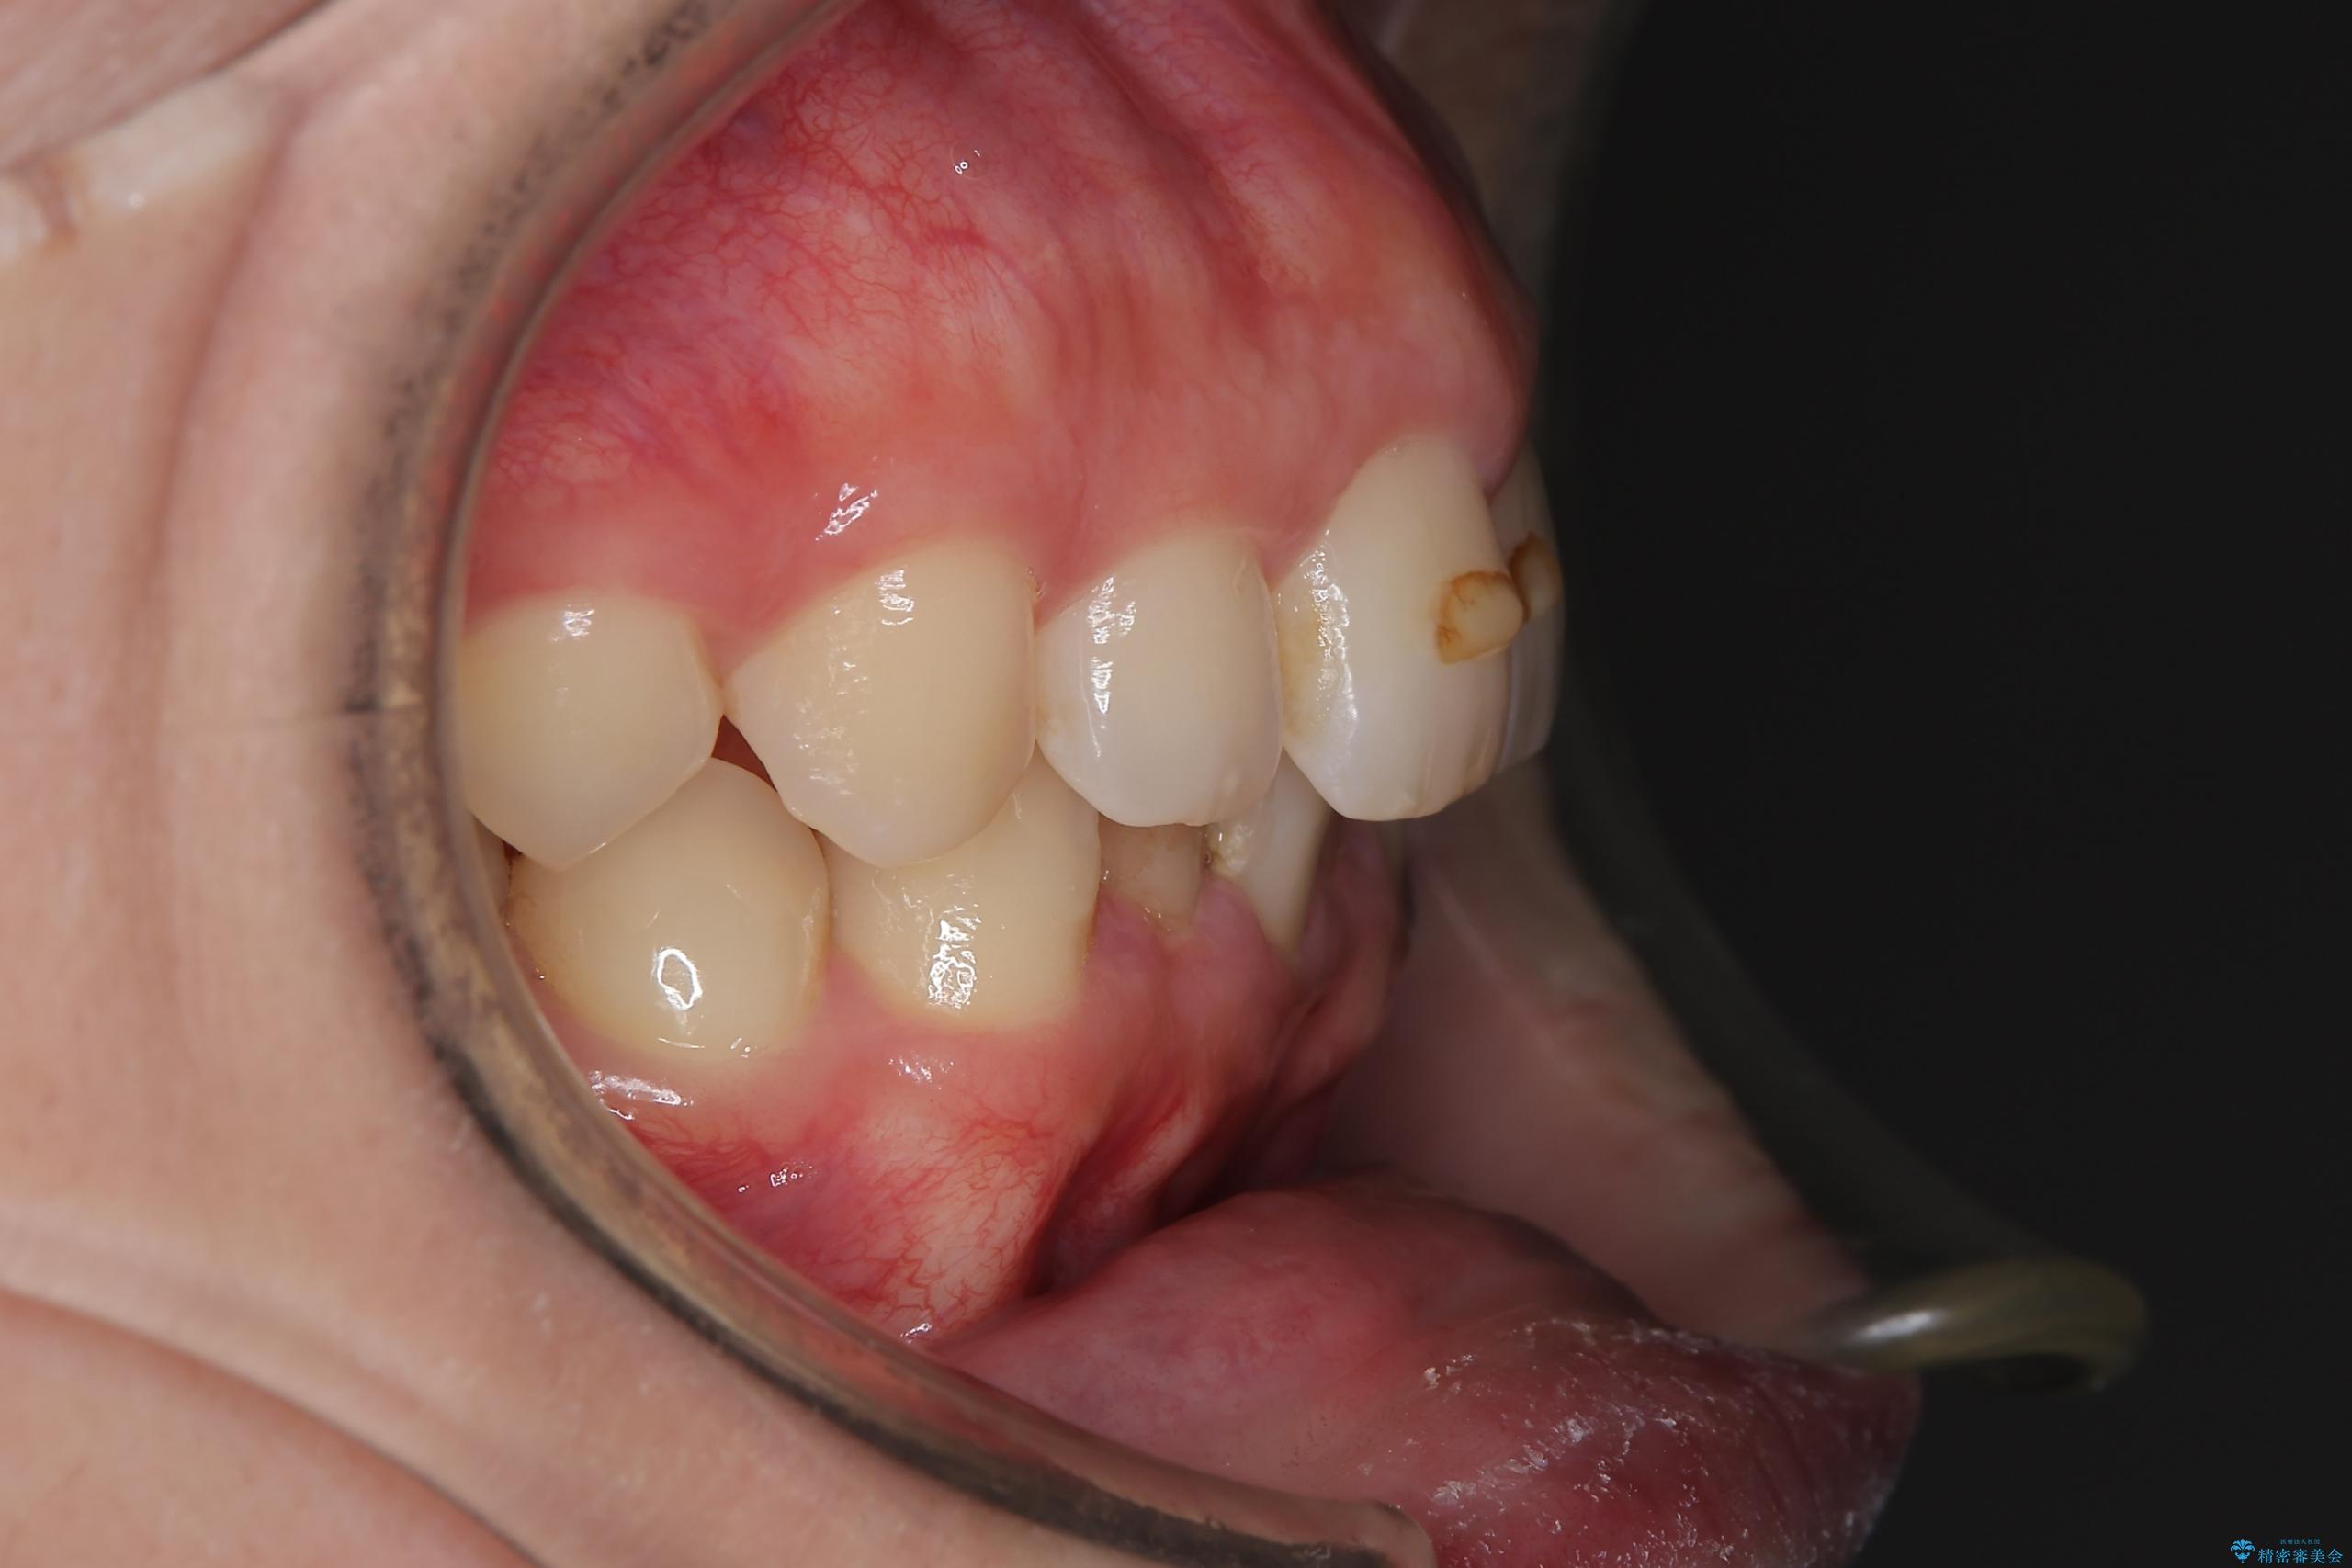

- 下の歯のがたつきを主訴に来院されました。

下の歯のがたつきと右の奥歯の噛みあわせ改善するために治療計画を立てることにしました。

右側臼歯部の咬合改善のために、臼歯部のみ部分的なワイヤー矯正を行い、咬合改善がみられてからインビザラインにて全体的な矯正を行なっていく治療計画を立てました。